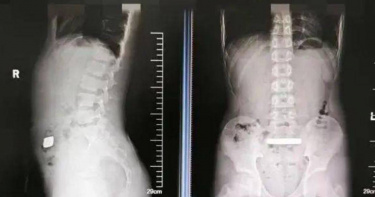

11歲弟腹脹送醫!X光驚見「高密度金屬」 醫取出100克金條傻眼

大陸江蘇省蘇州市11歲男孩小錢(化名)近日在家中玩耍時,不慎將一枚重100公克的金條吞入腹中。入院治療後,小錢無法自行排出金條,最終醫生只能透過手術干預,克服金條體積大、密度高、表面光滑等難點,僅用半小時便成功完整取出。《齊魯晚報》報導,在「吞金」後,小錢只感覺腹部輕微墜脹,並未出現劇烈疼痛或其他不適。家長發現後,立即帶其前往蘇州大學附屬兒童醫院急診科就診。經X片檢查,醫生發現一枚密度極高的金屬物體滯留於患者消化道內,結合病史診斷為「消化道異物」。由於金條體積較大,存在腸道梗阻及黏膜損傷等風險,急診醫生當即將小錢收治普外科,便於病情觀察及後續治療。入院後,小錢無腹痛腹脹、噁心嘔吐等表現,值班醫生決定先保守治療,給予促排便藥物,看金條能否自行排出。大陸江蘇省蘇州市11歲男孩小錢(化姓)近日在家中玩耍時,不慎將一枚重100公克的金條吞入腹中。(圖/翻攝自現代快報)不過,經過兩天的動態觀察,發現金條仍未能自然排出,再次複查X光片發現該異物位置沒有任何改變,可能固定或者卡在腸道內,小錢隨時有梗阻及穿孔的風險,應盡快從腸道中取出為宜。考慮患者年齡較小、腸道功能脆弱,傳統手術創傷大,醫院普外科果斷決定採用「內鏡下消化道異物取出術」進行干預。術中,醫師朱振偉、周小剛精準操控內鏡設備,克服異物體積大、密度高、表面光滑等難點,僅用半小時便成功將重達100公克的金條完整取出。手術後隔天,小錢已恢復正常進食,無任何併發症發生,順利康復出院。